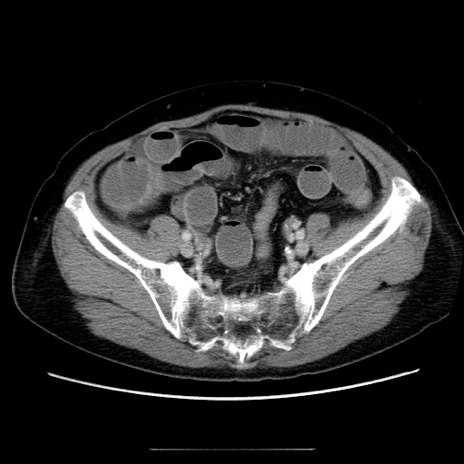

症例5(横断像)

【症例】70歳代女性

【主訴】お腹が張る

【現病歴】1週間くらい前から腹部膨満の自覚あり。昨日夜から増悪したため、本日救急外来受診。

【身体所見】意識清明、BT 36.5℃、BP 165/106mmHg、HR 80bpm、SpO2 98%、腹部:膨満、軟、自発痛・圧痛なし、触診にて不快感あり、腸蠕動音:減弱

【データ】WBC 12600、CRP 1.04